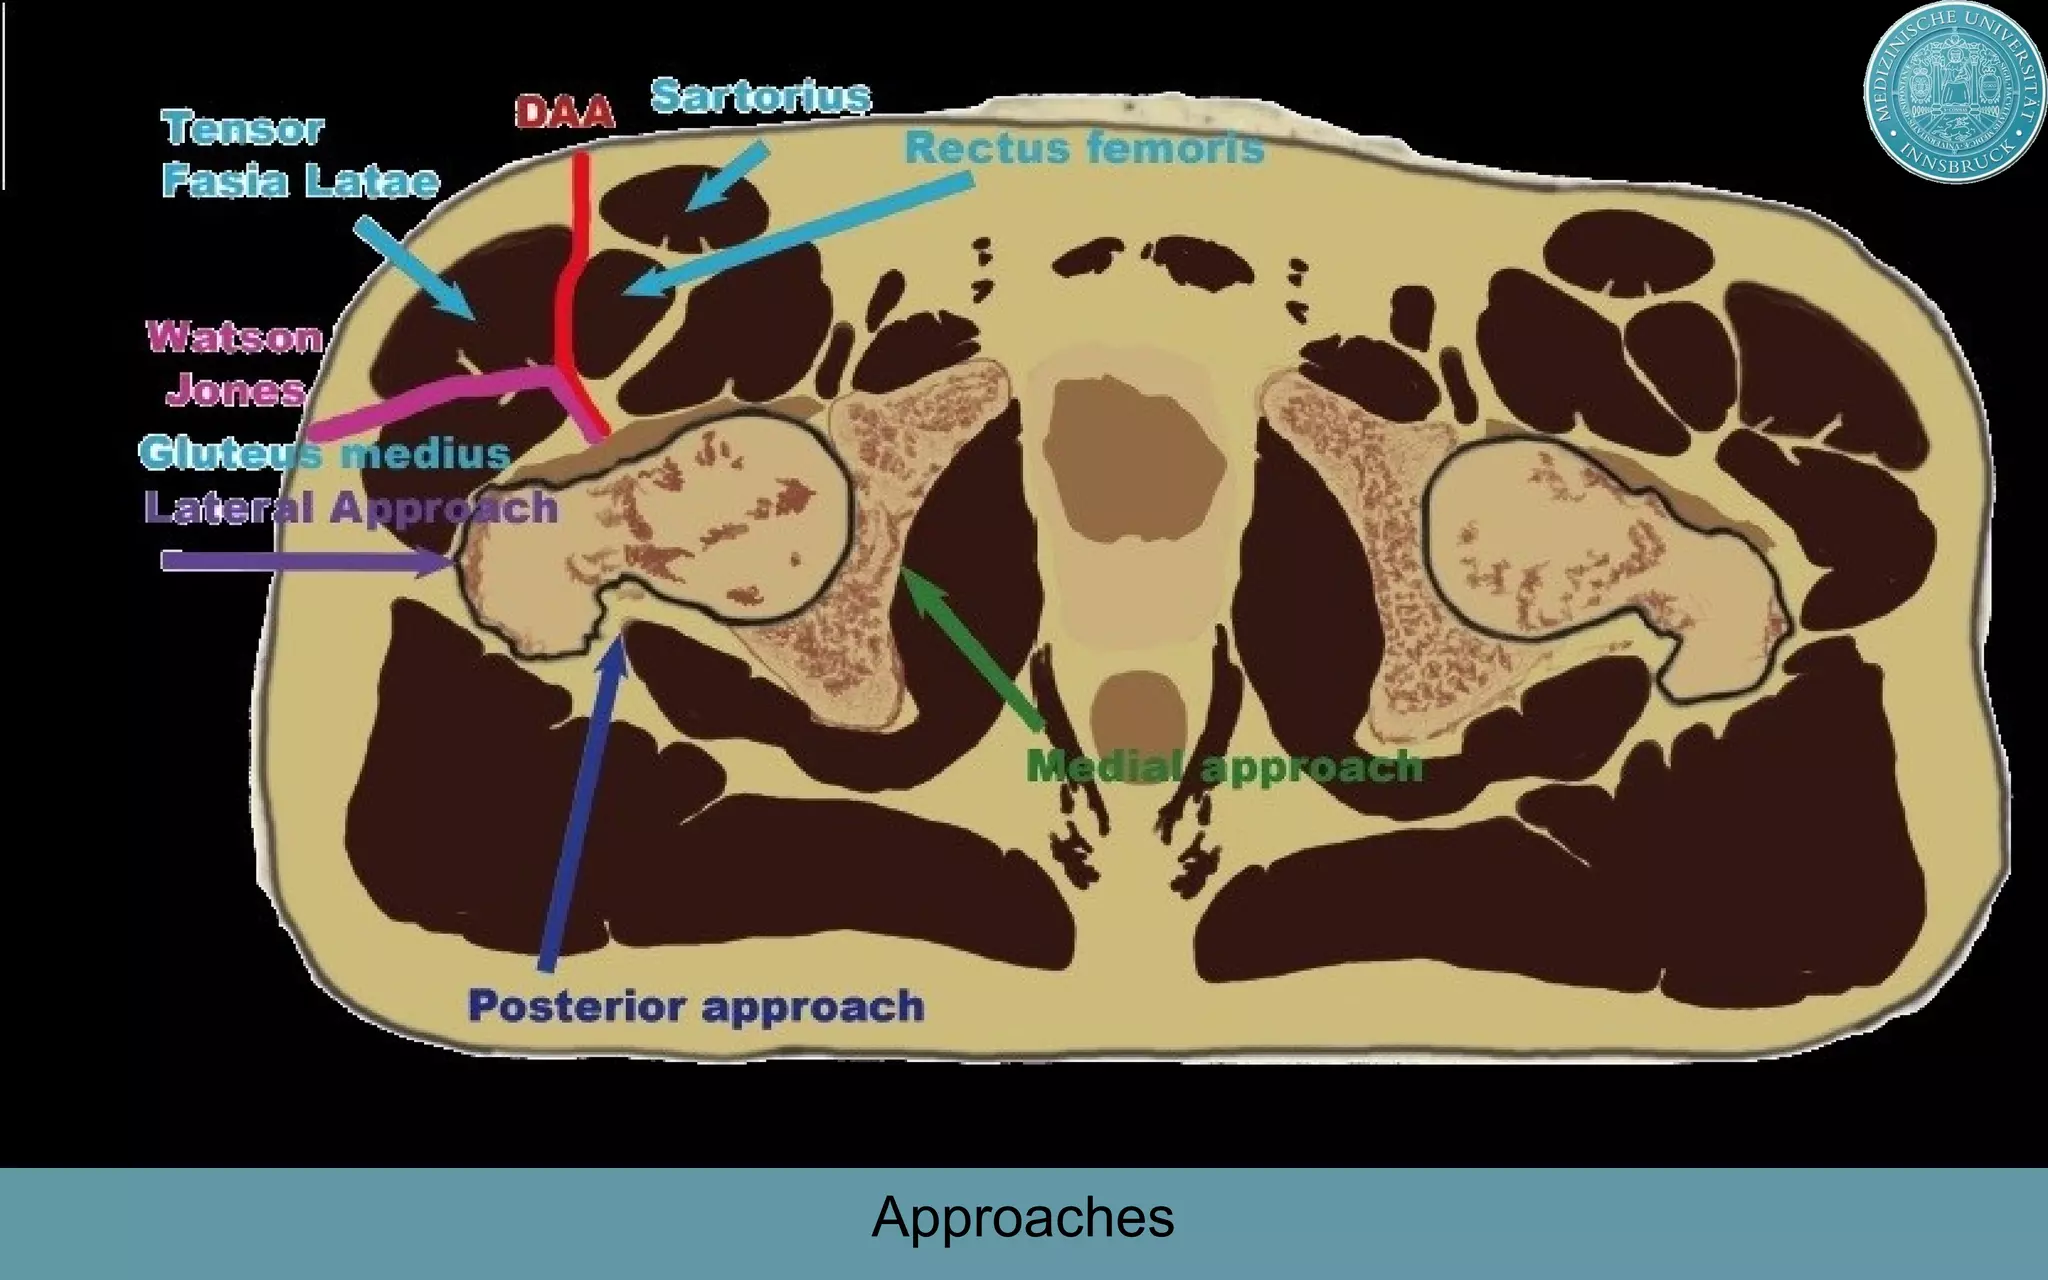

This document discusses the direct anterior approach for total hip arthroplasty. It lists advantages of the direct anterior approach such as increased stability, easier leg length equalization, lower costs by not requiring an operating table, reduced radiation exposure, faster rehabilitation, and lower risk of deep vein thrombosis. The document also discusses the historical background of the direct anterior approach, showing it has been performed since the 1880s. It presents images showing fatty degeneration of muscles and gluteal atrophy after total hip arthroplasty. Finally, it displays graphs comparing outcomes and improvements in quality of life domains between the direct anterior approach and minimally invasive approaches.